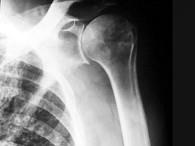

问题 女,71岁,左肩痛,系统性红斑狼疮服用高剂量的类固醇半年,结合图像,最可能的诊断是?(?)

选项 A.化脓性关节炎 B.类风湿关节炎 C.骨纤维肉瘤 D.肱骨头缺血坏死 E.肩关节结核

答案 E